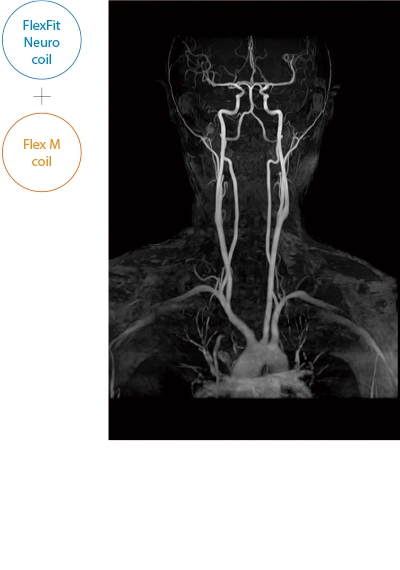

After the completion of MRA imaging, it automatically performs clipping for cerebral MRA. The automatic clipping identifies the extraction range based on the characteristics of the head. Additional clipping can also be performed on the images after the automatic clipping process.